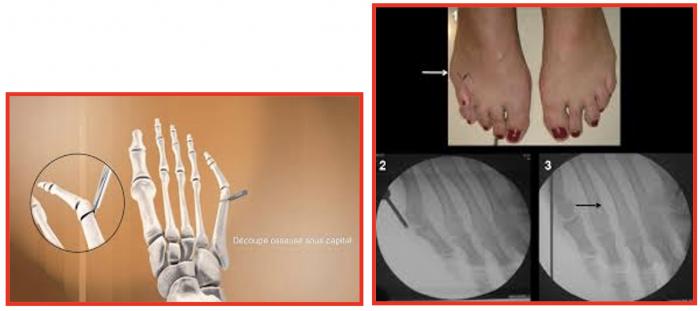

Les techniques « conventionnelles (ciel ouvert) » permettant, sous contrôle de la vue de corriger la déformation.

Au contraire, les techniques « percutanées » utilisent plusieurs incisions millimétriques, permettant le passage d’instruments spécifiques qui sont guidés sous la peau par un contrôle radiographique.

Les techniques « conventionnelles (ciel ouvert) » permettant, sous contrôle de la vue de corriger la déformation.Au contraire, les techniques « percutanées » utilisent plusieurs incisions millimétriques, permettant le passage d’instruments spécifiques qui sont guidés sous la peau par un contrôle radiographique.